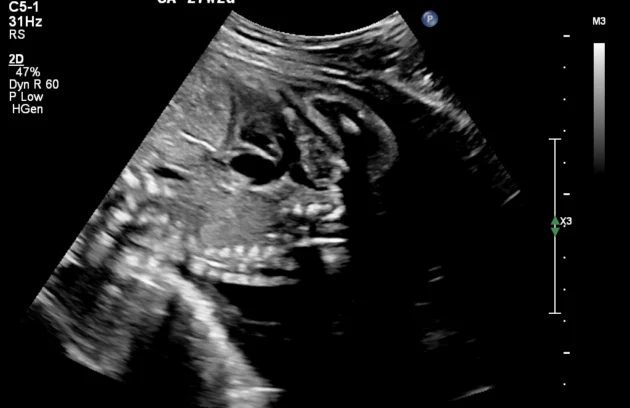

🔹 Anomaly Scan (Level II Ultrasound)

Anomaly Scan is a detailed ultrasound performed during pregnancy (usually between 18 and 22 weeks) to check the baby’s development. It helps detect structural abnormalities in the brain, heart, spine, kidneys, and other organs. This scan ensures your baby is growing normally and helps doctors identify any potential complications early. If you are looking for a reliable anomaly scan in Kathmandu, an early and accurate diagnosis is essential for a safe pregnancy.